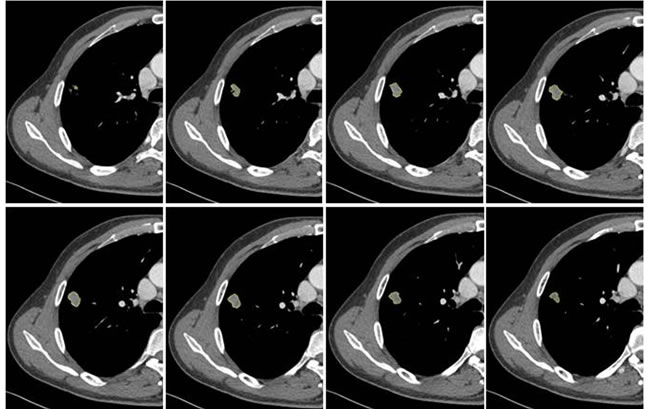

Figure 3: Example of CT images showing segmentation of lung tumor. Semiautomatic tumor segmentation was done on every slice of the tumor using 3D slicer (a), and the 3D view of the segmented tumor (b) which was shown in yellow.

CT image analysis and post-processing

Two radiologists (with 6, and 3 years’ experience in thoracic CT imaging, respectively), who were blinded to clinical and histiopathological data, reviewed all CT images separately. They were asked to identify pulmonary lesions and to evaluate the enhancement heterogeneity according to the following criteria: homogeneous enhancement was defined as more than 90% of the tumor area was occupied by the same CT attenuation as ascertained by visual assessment; otherwise heterogeneous enhancement was considered (Figure 2). In case of disagreement, the third reviewer with 27 years of clinical experience in thoracic imaging, made the final decision. Then, semiautomatic tumor segmentation was done in consensus by three radiologists using a designated multi-platform, free and open source software package for visualization and medical image computing (3D slicer, version 4.4.0; available at: http://slicer.org/) (Figure 3). Totally, 54 features were extracted and they were divided into four categories (Supplementary Table 1, Image features metrics are available at: https://www.slicer.org/wiki/Documentation/Nightly/Modules/HeterogeneityCAD), including (1) First-Order Statistics, (2) Morphology and Shape, (3) Texture: GLCM, and (4) Texture: GLRL.